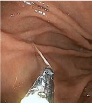

内視鏡で、胃粘膜に刺⼊しているアニサキス発⾒。

捕まえて引っ張っています。その後摘出されました。